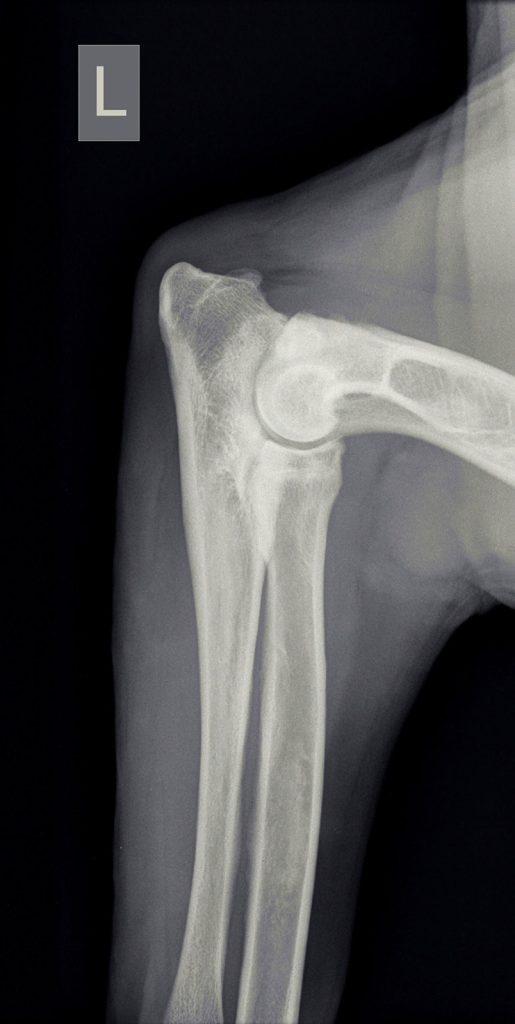

Bij het navoelen van de poten bleek hij erg gevoelig bij druk op de botten van de onderarm, maar niet gevoelig aan de gewrichten of aan de andere poten. Voor de zekerheid werden er röntgenfoto’s genomen om te achterhalen wat er aan de hand was. Op de röntgenfoto’s bleek er midden in de botten van de onderarm wolkvorming te zijn ontstaan. Dit kan passen bij een aandoening genaamd enostose, oftewel groeipijn.